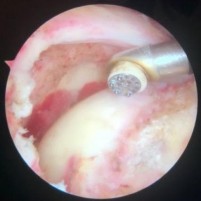

Mài vùng diện bám của gân nhưng không mài hết phần vỏ xương cứng.

Hình 2.20. Sau mài bộc lộ diện bám của gân

* Nguồn: ảnh chụp trong mổ của BN Lê Trọng T, mã số bệnh án 19035084